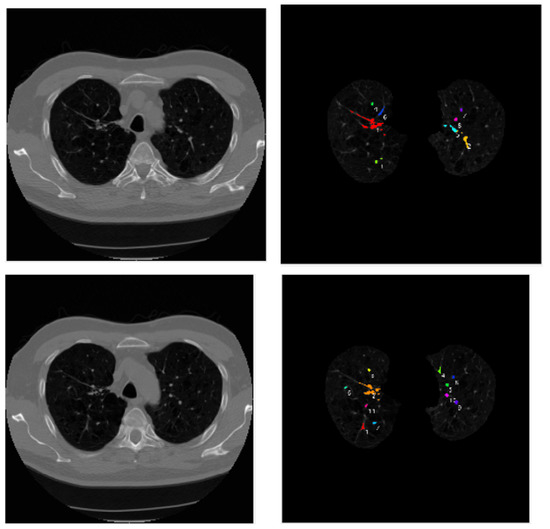

3.1. Data Pre-Processing